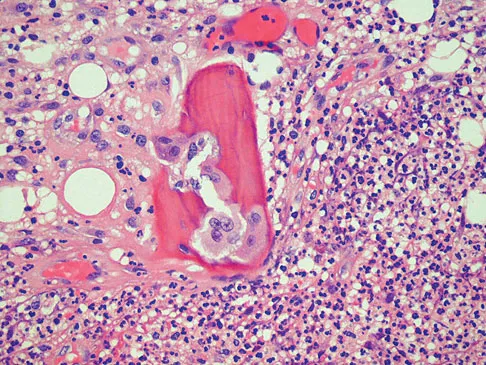

A 38-year-old man has an enlarging left paraspinal soft-tissue mass. Based on the MRI scans and biopsy specimens shown in Figures 32a through 32e, what is the most likely diagnosis?